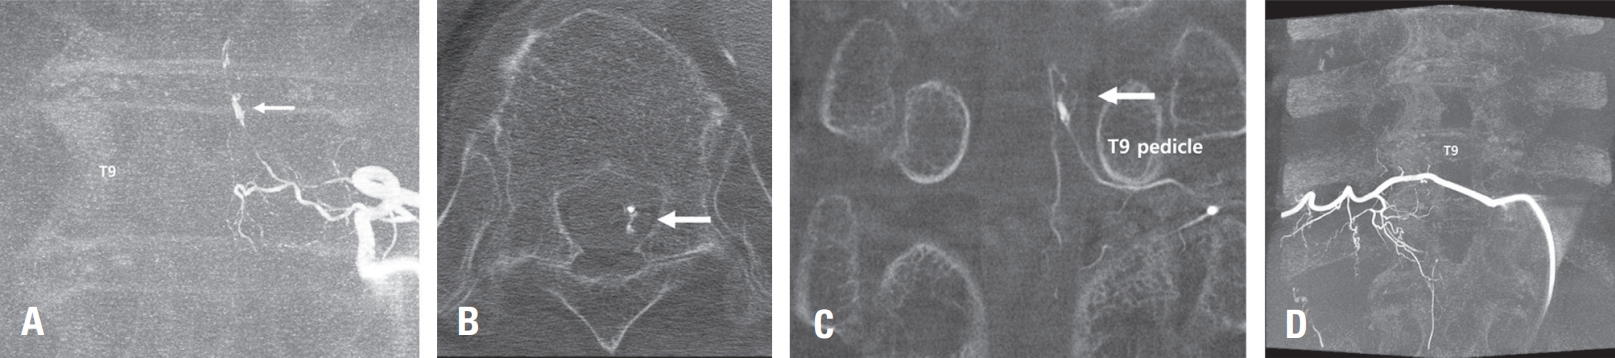

Fig. 2.

Angiogram of the left T9 intercostal artery in the left anterior oblique view showing a focal fusiform dissecting aneurysm in left T9 radiculopial artery (A, arrow). 3-dimention reconstruction of CT angiogram showing 2 mmx2.5 mm sized aneurysm and network of vessels in relation to left T9 pedicle (B, C, arrow). Followup angiography was performed after POD 4 weeks and confirmed the non-visualization of aneurysm sac and feeding artery from left T9 radiculopial artery the complete absence of the aneurysm (D).

A 71-year-old female patient presented to a local clinic with sudden onset headache and back pain on the day of admission. A brain computed tomography (CT) scan performed at the local clinic diagnosed subarachnoid hemorrhage (SAH) in the basal cistern (Fig. 1A). 3-dimention CT brain angiography was conducted but failed to identify the source of the hemorrhage (Fig. 1B). Consequently, the patient was transferred to our hospital for further evaluation and management. Upon arrival, the patient complained of severe back pain. To investigate the potential spinal origin of the hemorrhage, a contrast-enhanced Magnetic Resonance Imaging (MRI) of the thoracic spine was performed. This revealed an abnormal intradural extramedullary heterogenous lesion located in the T8/9 level suspected as the source of bleeding (Fig. 1C, D, E). Immediately, spinal angiography of the thoracic spinal vascular lesion was performed. Spinal angiography revealed the fusiform aneurysm on a distal segment of a radiculopial artery of the left intercostal artery at left T9 (Fig 2A, B, C). However, the feeding artery was found to be too narrow, precluding endovascular procedures such as embolization.

The patient then underwent surgical treatment on the subsequent day. Under general anesthesia, a total laminectomy was performed at thoracic levels 8 and 9, exposing the dura. After dural incision, a relatively small amount of subdural hematoma was identified, and a portion of it was removed. An acute bleeding focus was identified from the radicular artery beneath the left T9 nerve root. Following resection of the T9 root, the surrounding radicular artery was occluded with a clip for hemostasis. Postoperatively, the patient’s severe back pain significantly improved, and she was able to ambulate, leading to discharge in a walking state. Four weeks later, a follow-up Digital Subtraction Angiography (DSA) of the surgical site was performed, confirming the complete absence of the aneurysm (Fig. 2D).